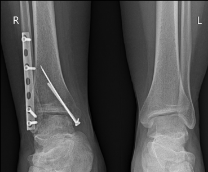

У вас в ноге теперь конструкция из пластин и/или спиц.